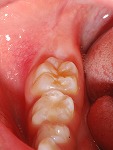

~シーラント~

小児歯科

術前

術後